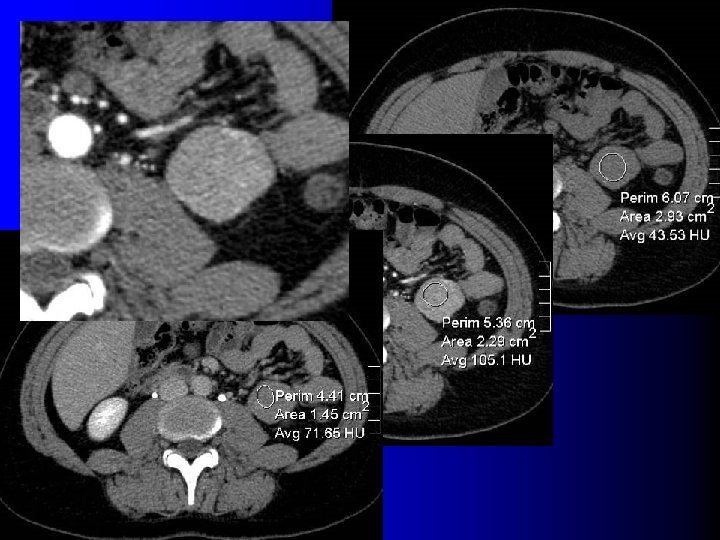

Tomodensitométrie Tumeur hypervasculaire avec plages de densité graisseuse (-10 UH à -100 UH) l l Intérêt : – Diagnostique – Thérapeutique : l Taille exacte l Localisation l Importance du contingent vasculaire l Technique d'examen rigoureuse: – Minimiser les effets de volume partiel l Coupes fines (millimétriques) l Examen sans injection

Tomodensitométrie Tumeur hypervasculaire avec plages de densité graisseuse (-10 UH à -100 UH) l l Intérêt : – Diagnostique – Thérapeutique : l Taille exacte l Localisation l Importance du contingent vasculaire l Technique d'examen rigoureuse: – Minimiser les effets de volume partiel l Coupes fines (millimétriques) l Examen sans injection

TDM: cas des AML très vasculaires l Très nombreux vaisseaux dysmorphiques – Washout précoce – Diagnostic: l l Contexte (STB, LAM) Micro-anévrysmes visibles en TDM

TDM: cas des AML très vasculaires l Très nombreux vaisseaux dysmorphiques – Washout précoce – Diagnostic: l l Contexte (STB, LAM) Micro-anévrysmes visibles en TDM